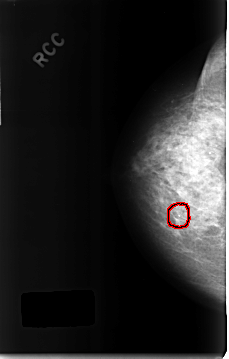

C_0315_1.RIGHT_CC

RIGHT_CC LINES 4656 PIXELS_PER_LINE 2968 BITS_PER_PIXEL 12 RESOLUTION 50 OVERLAY

FILE: C_0315_1.RIGHT_CC.OVERLAY

TOTAL_ABNORMALITIES 1

ABNORMALITY 1

LESION_TYPE CALCIFICATION TYPE PLEOMORPHIC DISTRIBUTION CLUSTERED

ASSESSMENT 4

SUBTLETY 4

PATHOLOGY BENIGN

TOTAL_OUTLINES 1

BOUNDARY